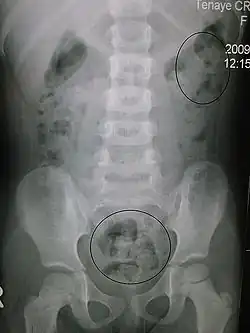

In order to correctly manage neurogenic bowel dysfunction it is important to accurately diagnose it. This can be done by a variety of methods, the most commonly used would be taking a clinical history and carrying out physical examinations which may include: abdominal, neurological and rectal examinations.[26] Patients may use the Bristol Stool Chart to help them describe and characterise the morphological features of their stool, this is useful as it gives an indication of the transit time.[27] An objective method used to evaluate the motility of the colon and help with diagnosis is the colon transit time.[28] Another helpful test to diagnose this condition may be an abdominal X-ray as this can show the distribution of feces and show any abnormalities with the colon, for example a megacolon.[16]